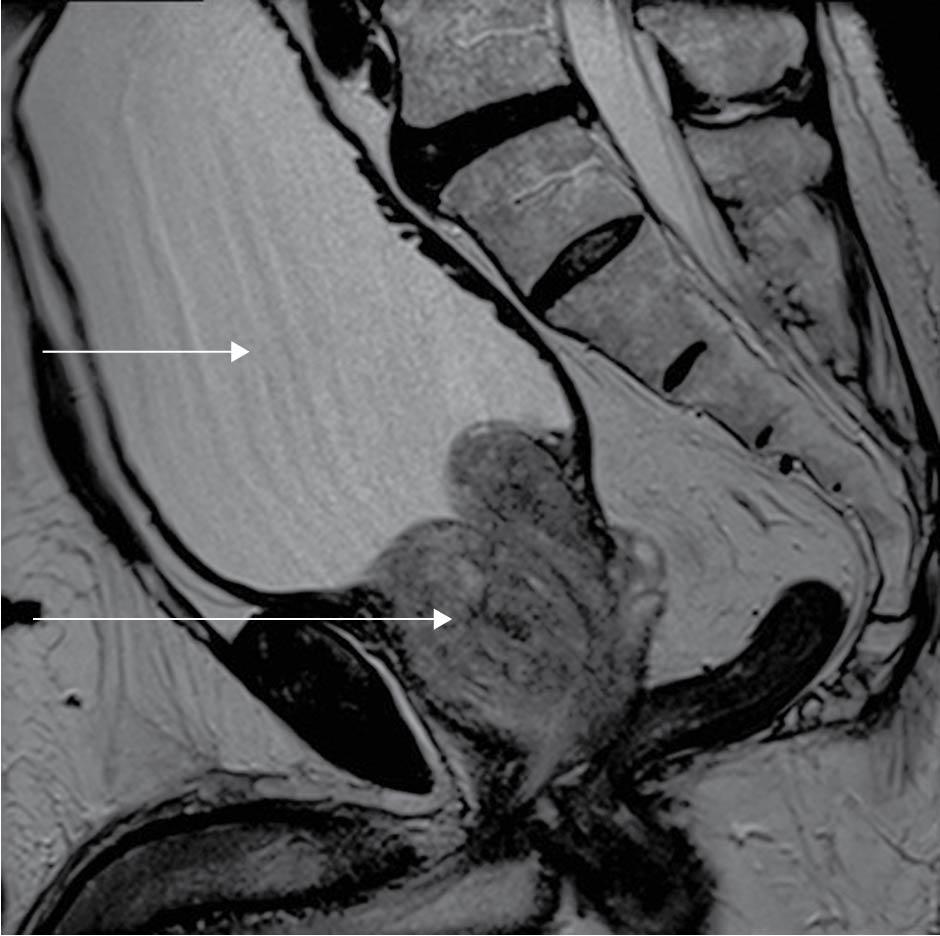

Prostatic enlargement ( Fig. 59 )